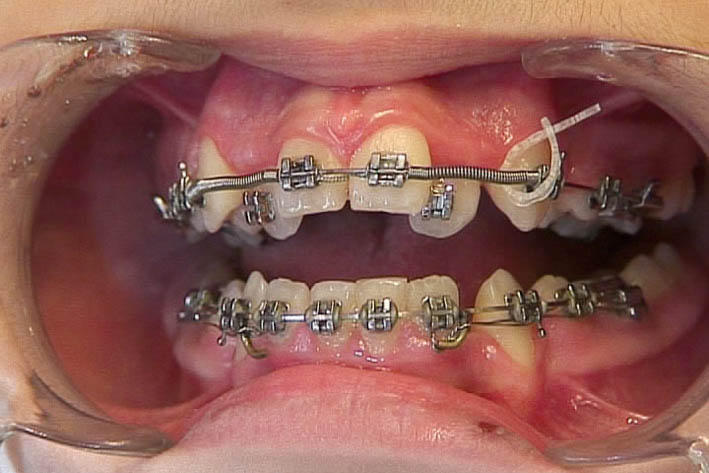

بعد از ایجاد فضا برای لترالهای کراس (شکل 157-1) حدود ده حلقه از چینالاستیک را بریده و آن را دور آرچوایر قرار دهید (شکل 158-1). حلقه انتهایی را به کمک پلایر سپراتور گشاد و سر دیگر چینالاستیک را از داخل آن رد میکنیم (شکل 159-1).

مابقی حلقهها را بغیر از آخری بریده و آن حلقه را روی براکت لترال قرار میدهیم تا نزدیک قوس فکی بشود (شکل 160-1).

شکل 157-1: بعد از باز شدن فضا برای لترال میتوانید از چین الاستیک برای نزدیک کردن لترال به قوس استفاده کنید.

شکل 158-1: چند حلقه از چین الاستیک را دور آرچ وایر قرار دهید.

شکل 159-1: قلاب کردن چین الاستیک دور آرچ وایر

شکل 160-1: درگیر کردن یک حلقه از چین الاستیک به براکت لترال تا دندان به قوس فکی نزدیک شود.

در زمان نزدیک شدن لترال به قوس فکی اگر به دندانهای پائین گیر کند باید از بایت پلیت خلفی (کامپوزیت روی کاسپهای باکال 7های پایین) استفاده کنید (شکل 161-1).